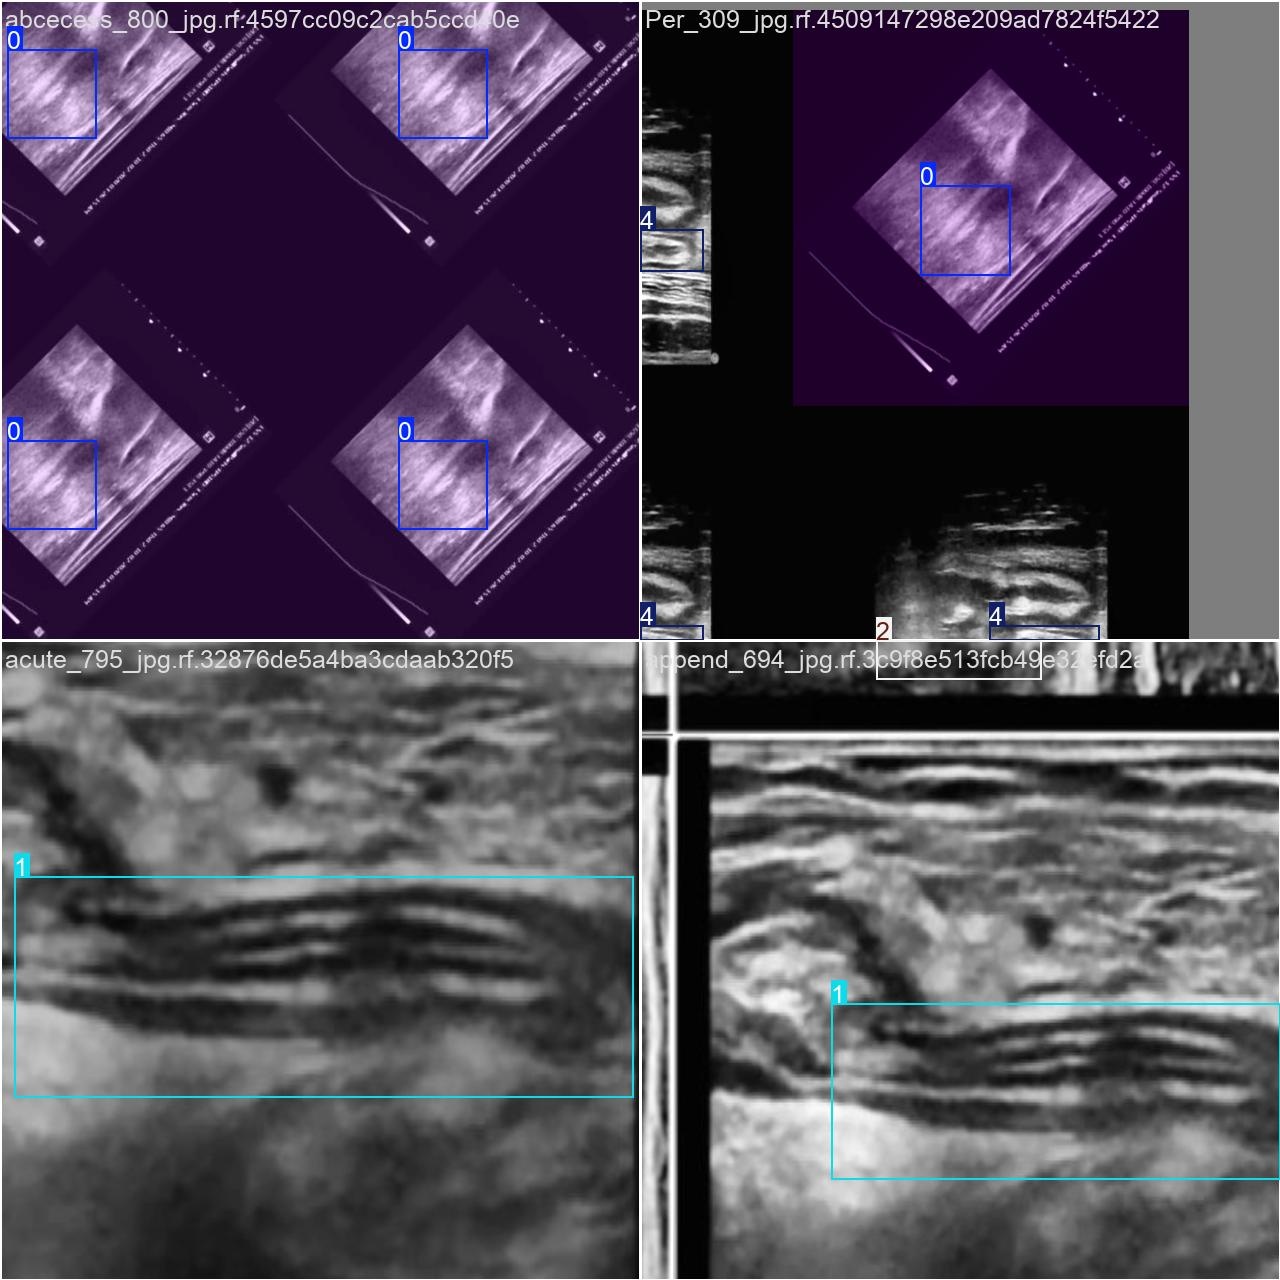

部分数据集图像如下图所示:

部分标注如下图所示: